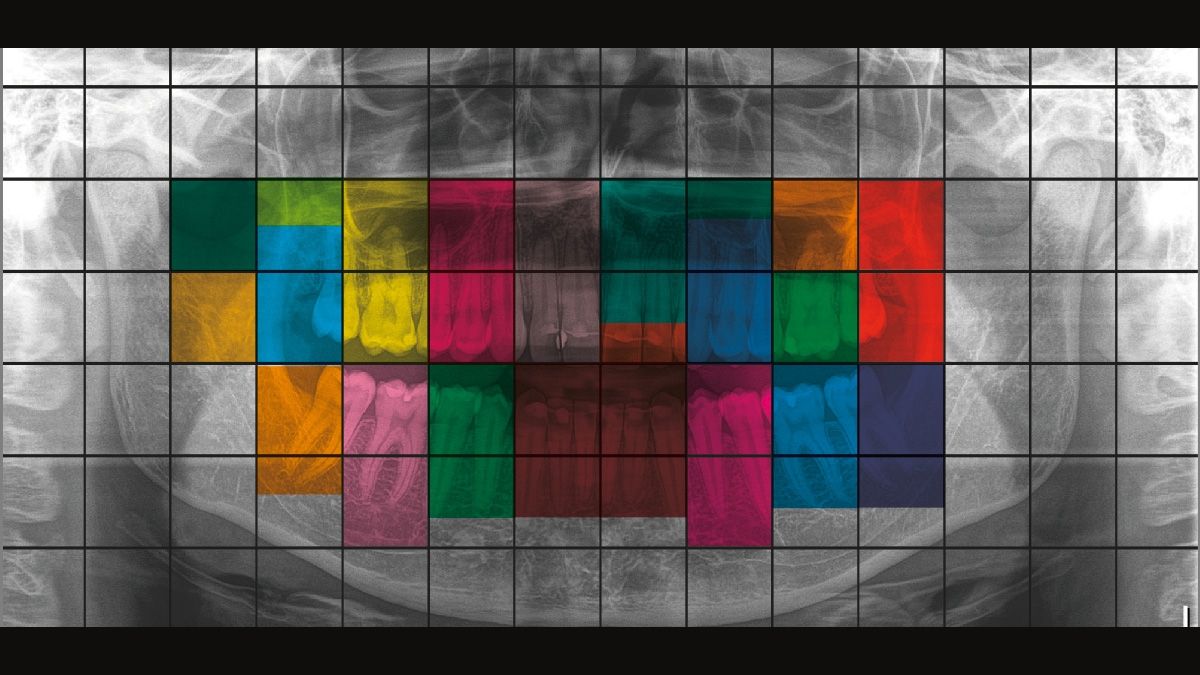

该图像显示了多张使用和不使用DCS技术的X射线图像。通过对图像的控制,亲自查看DCS传感器对图像质量的影响。